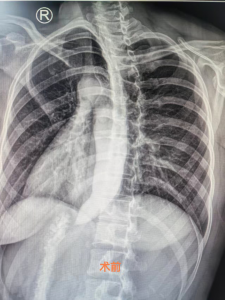

近日,她找到我院消化内科主任张宝华主任医师就诊,张主任详细了解病史后,为她完善了食道吞碘造影检查,结果显示食道贲门变窄呈“鸟嘴征”,造影剂通过受阻,考虑食道贲门失弛缓症,行胃镜检查不排除贲门失弛缓症。结合病史及辅助检查,陈女士被确诊为贲门失弛缓症。

今年1月下旬,在患者及家属知情同意后,麻醉科团队密切配合,由张华宝主任医师带领指导内镜手术团队,谭巧玫副主任医师经过1个多小时的努力,成功为陈女士完成POME手术。术后第二天陈女士可以流质饮食,长期困扰她的吞咽困难症状消失,Eckardt评分0分。复查食道吞碘造影提示造影剂顺利通过贲门进入胃内,恢复良好,目前已康复出院。